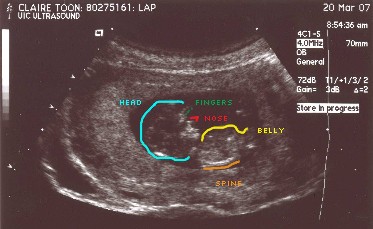

Here are the first pictures of Baby Zen. These ultrasound pictures were taken a few weeks ago at 12 weeks. I don't know about you, but sometimes the ultrasound pictures don't look like much of anything. I've included a guide picture to help you see Baby Zen. Just click on the pictures to make them larger.